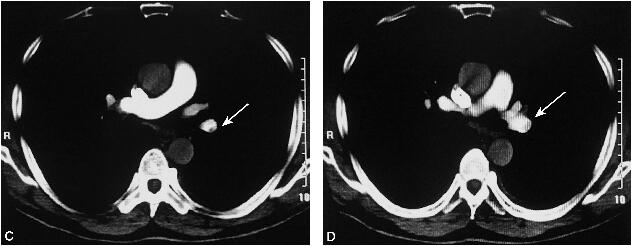

患者胸腔积液提示渗出液,反复多次查结核及恶性疾病均证据不足,但查见大量嗜酸性粒细胞。进一步追问病史,患者发病前无明确疫水、疫情和石棉接触史,未服用特殊药物;结合胸痛、D-二聚体高,氧分压低,因此需行CT肺动脉造影排查急性肺栓塞。肺动脉CTA如图2所示。

图2 肺动脉CTA

左肺上叶尖段、舌段肺动脉、左肺下叶各段级肺动脉多发栓塞灶(白箭)